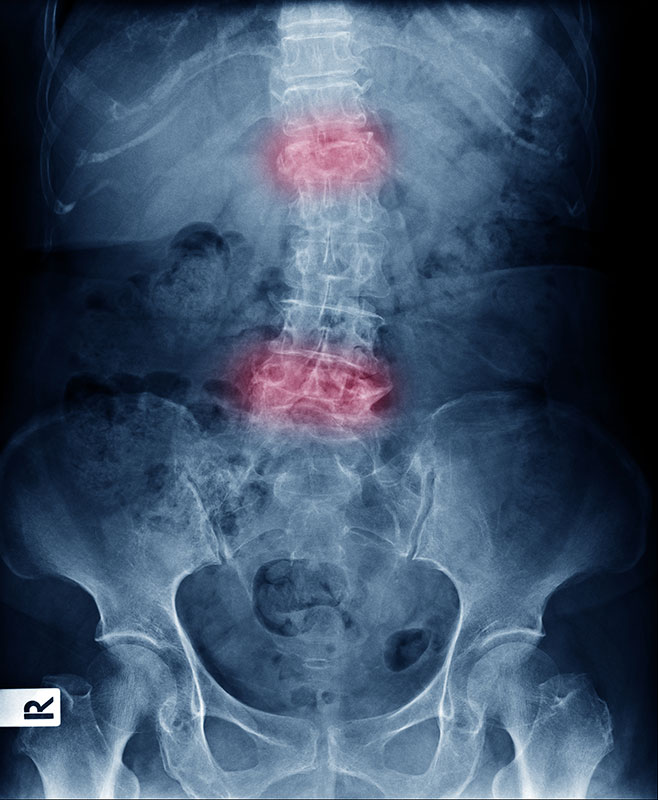

Imaging

Radiology imaging such as X-rays allow your provider to check for changes or abnormalities in joints and bones that may indicate AS. MRI may also be used to provide more detailed imaging of bones and soft tissues.